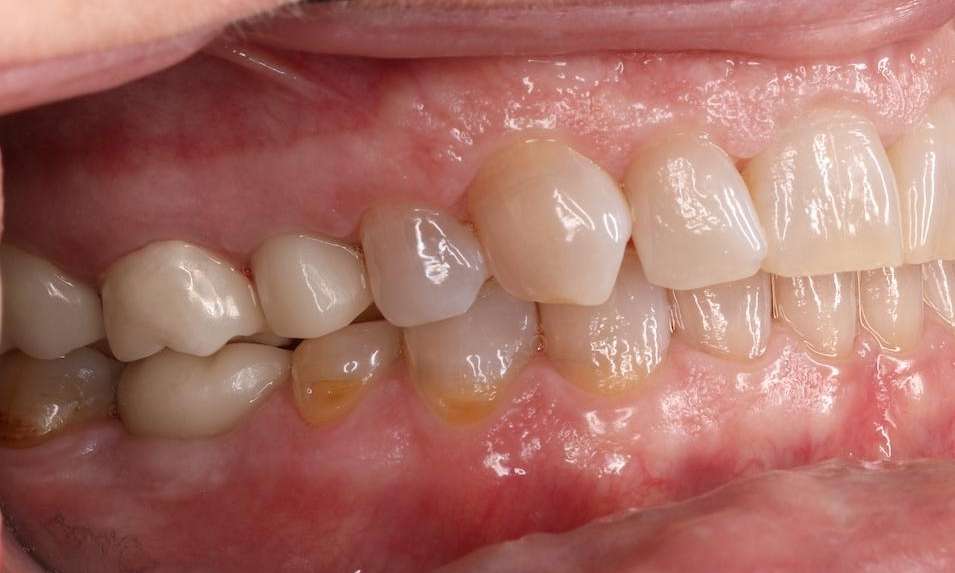

This patient was missing a molar and pre-molar, the workhorses for comfortable chewing. Without these stronger teeth at the back of your mouth, it becomes difficult to properly chew and eat your food.

Two dental implants saved the day by replacing both their root and tooth so this patient can comfortably chew their food again.

Close up of mouth before dental implants, nashville tn Close up of mouth after dental implants, nashville tn